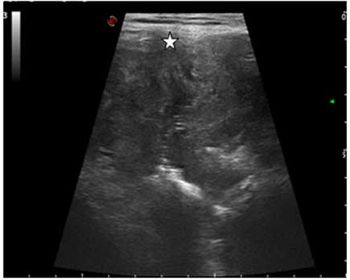

Case History: 60-year-old male with complaints of inability to pass stool and flatus with pain in abdomen.